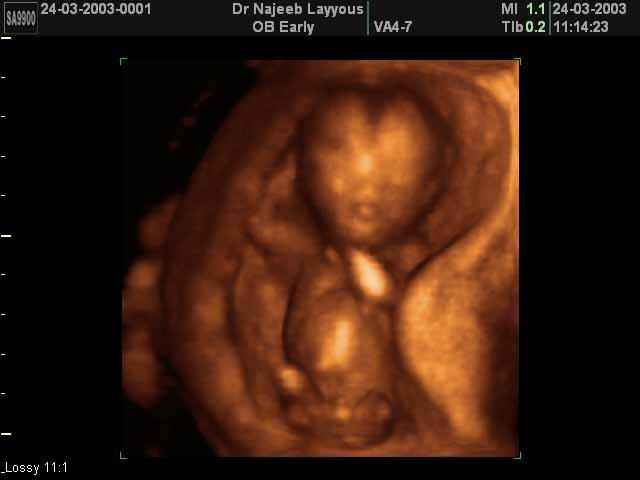

- 3D Photos Ecographie du Premier Trimestre

3D Photos Ecographie du Premier Trimestre (Photos d’échographie de tôt grossesse)| Dr N Layyous